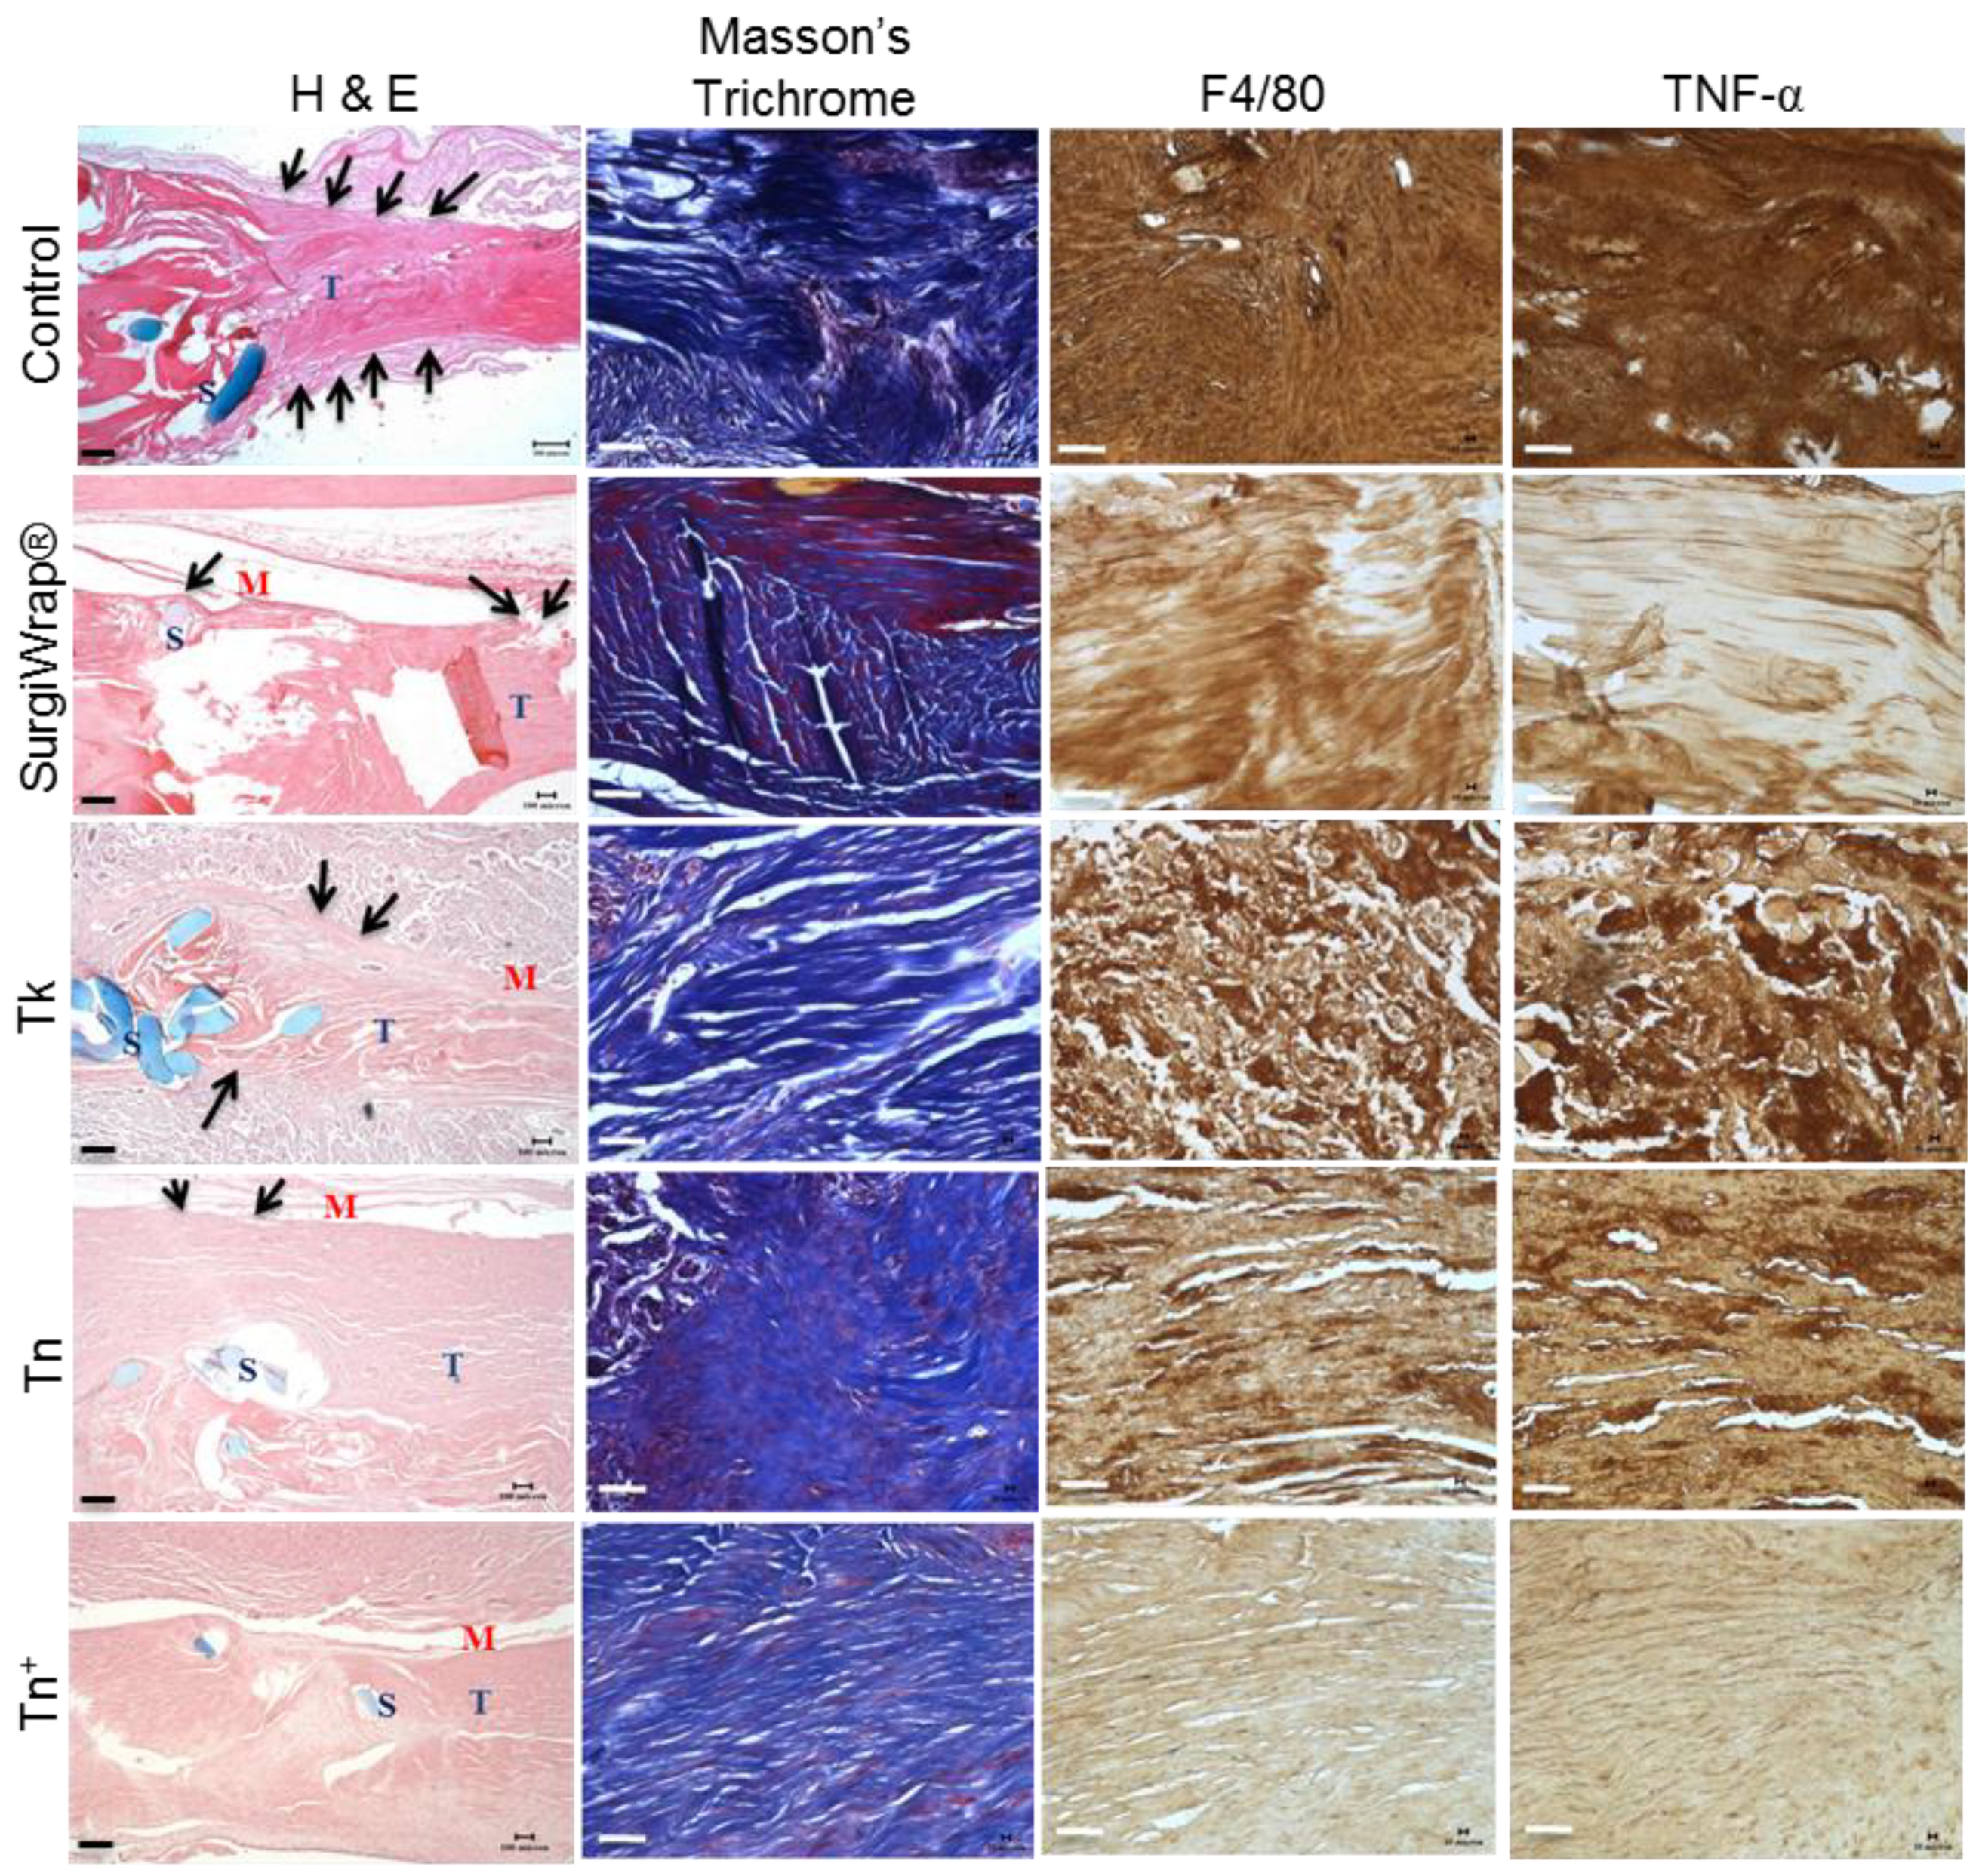

2.4. In Vivo Studies